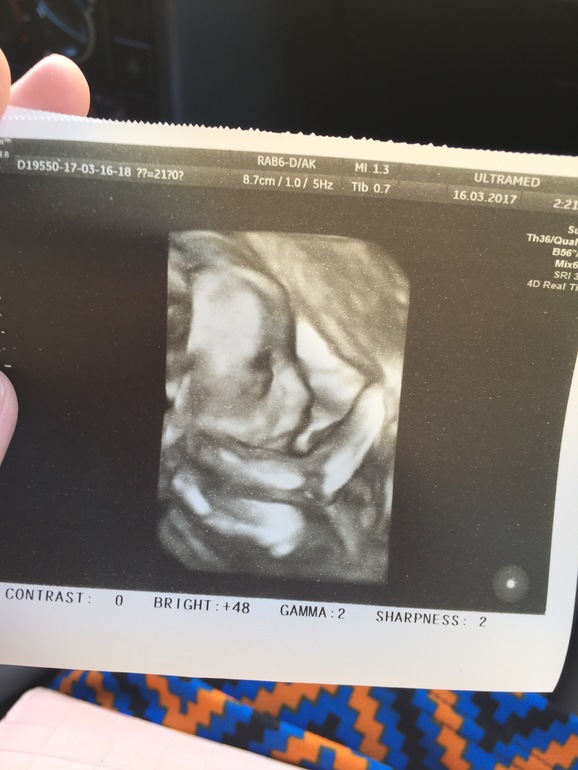

22 недели, второй скрининг, вопросы! +фото дочи)

Мои неделькиДевочки всем привет) у нас уже 22 недели без парочки дней, сходили на второй скрининг, у нас все отлично, малышка весит почти 400гр, кровотоки, матка, плацента и тд, все в норме! Врач доволен)) вопрос наверное к опытным мамам, я начала писать списки, что покупать в аптечку малышке/ для гигиены/ в род дом и тд. Вопрос по аптечке, что вам пригодилось? Я написала стандартные йод, зеленка, перекись и тд, плюс антигистаминное, против коликов, аспиратор, аквалор, бепантен и жаропонижающее. Подруга говорит что не нужно все покупать, мол по мере необходимости. А я считаю, что лучше иметь в запасе, чем потом среди ночи бегать по аптекам. Все ли нужно, что я написала? П.с.ну и фото зайки нашей)